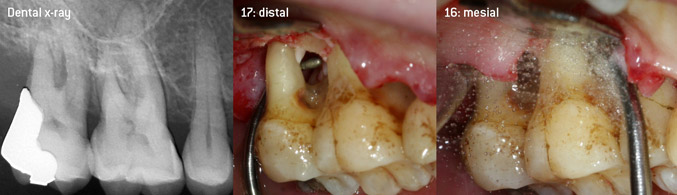

En tant qu'initiateurs du développement du nouvel insert détartreur à air N° 3AP avec un revêtement diamant, les deux dentistes ont reconnu la nécessité d'améliorer les restrictions de manipulation des inserts avec un revêtement diamant disponibles dans le commerce, en particulier lors du traitement des furcations et du travail dans des poches intra-osseuses étroites. Cela devrait être possible pour les procédures non-chirurgicales (figure 2) et chirurgicales (figure 3).

Débridement ouvert des furcations sur les dents 16 et 17

Figure 3 : Débridement ouvert des furcations sur les dents 16 et 17 en cas de perte d'attache avancée

L'objectif était de développer un insert universellement applicable afin d'éviter les changements d'insert qui prennent du temps. En outre, il devrait être plus facile d'utiliser les nouveaux inserts dans les poches intra-osseuses étroites à partir de l'entrée distale et à l'entrée distale de la furcation des molaires maxillaires, ce qui permettrait une utilisation plus efficace des instruments. Pour ce faire, une courbe d'instrument de plus grand diamètre a été utilisée (figure 1), ce qui est très avantageux pour le débridement fermé des dents présentant une perte d'attache avancée et une implication de la furcation en particulier (figure 4).